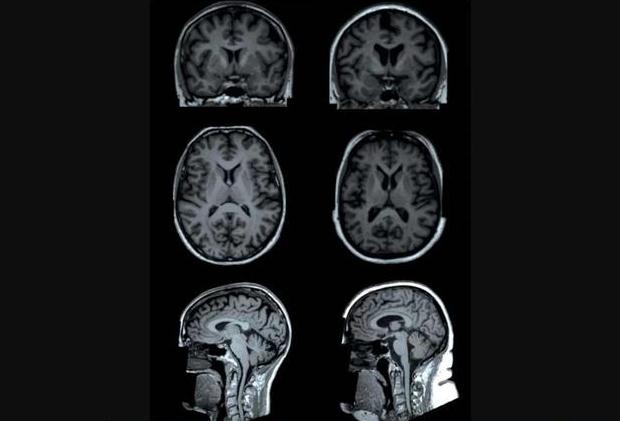

一項最新研究發(fā)現(xiàn),體脂越高,大腦某些區(qū)域容量就越小。上圖為研究中兩名測試者(年齡均為65歲的女性)的大腦核磁共振掃描。一名測試者(左側圖)體脂為13%,另一名測試者(右側圖)體脂為49%。核磁共振掃描顯示,與左圖測試者相比,右圖測試者大腦某些區(qū)域(“皮質下區(qū)域”)灰質容量較低。

新浪科技訊 北京時間4月28日消息,據國外媒體報道,肥胖與身體諸多有害影響有關,目前,最新一項研究表明,肥胖還可能影響大腦結構,研究人員分析大腦掃描數據,發(fā)現(xiàn)體脂越高,腦容量就越小。他們指出,尤其是身體脂肪過多與灰質容量減少有關,灰質是包含神經細胞的大腦組織,位于大腦中心區(qū)域。

4月23日發(fā)表在《放射學》雜志的一項研究表明,與女性相比,男性體脂與大腦容積之間的關聯(lián)性更密切。荷蘭萊頓大學醫(yī)學中心研究人員發(fā)現(xiàn),與體脂有關的大腦白質——長神經纖維,可促使大腦各個區(qū)域進行交流。

越來越多的研究表明,肥胖與大腦變化有關,其中涉及腦容量較低或者腦萎縮。之前研究也發(fā)現(xiàn),肥胖與癡呆癥等大腦疾病之間存在關聯(lián)性,盡管如此,這項最新研究只表明體脂與較低腦容量之間的聯(lián)系,并不能證明過多體脂實際會導致腦萎縮。研究報告作者稱,我們需要更深入地研究這種關聯(lián)性,并確定減肥是否對大腦有益。

在這項最新研究中,研究人員分析了英國12087位測試者的信息數據,他們平均年齡62歲。測試者接受核磁共振掃描,用于評估大腦灰質和白質結構,同時,研究人員還使用一種叫做“生物電阻抗(bioelectrical impedance)”的方法測量了測試者體脂指數,生物電阻抗是一種通過身體釋放小電流評估一個人體內脂肪含量的方法。

研究人員發(fā)現(xiàn),體脂較高男性與灰質整體容積較少有關,同時與大腦中心某些較少容積灰質區(qū)域有關。這涉及到丘腦、尾狀核、海馬體、蒼白核、殼核和伏核,其中一些區(qū)域參與大腦的獎勵回路,另一些區(qū)域幫助調控身體運動,對于女性群體而言,她們只存在體脂與蒼白核容量減少相關聯(lián)。對于男性和女性群體而言,與那些較低體脂者相比,較高體脂者與大腦白質微觀結構差異有關。

目前科學家尚不清楚為什么體脂指數與腦容量減少或者白質差異有關,一種解釋觀點認為,較高體脂可能產生損害大腦組織的炎癥。研究人員稱,研究中較少腦容量可能表明該區(qū)域神經元損失。

盡管如此,由于這項研究是在某一時間點進行的,目前還不清楚肥胖是否會改變大腦,還是某些大腦灰質容量較少的人容易肥胖。研究人員稱,未來研究應當及時跟蹤分析人體脂肪變化是否會導致大腦結構變化。(葉傾城)